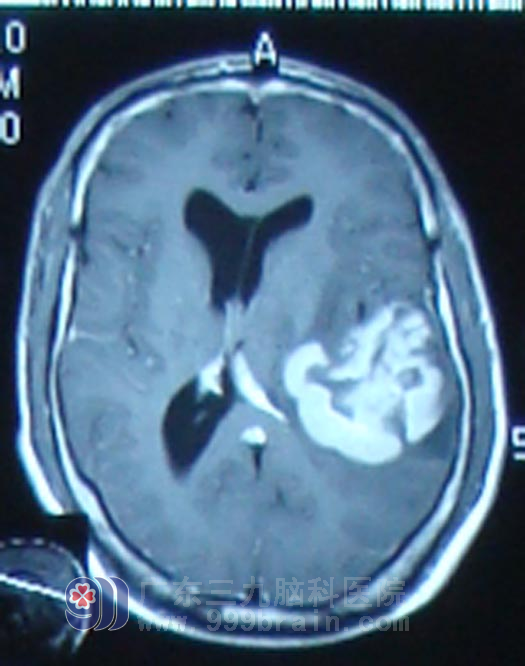

患者朱先生, 35岁,2011年10月21日无诱因出现头痛不适,且程度剧烈,伴言语不清,但是未予重视4天之后头痛正传未见缓解,还出现了呕吐数次,出现“癫痫”症状,表现为四肢抽搐,头后仰,双眼紧闭,持续2-3秒之后自行缓解,当地医院头颅CT及MR显示左颞叶占位,10月28日即来广东三九脑科医院就诊,来院时,朱先生神志清楚,不完全性失语,右侧肢体肌力稍减弱。完善相关检查且排除手术禁忌症后,11月4日行手术治疗,手术部分切除,术后病理为弥漫性大B细胞淋巴瘤,术后症状好转后转入肿瘤综合治疗中心行大剂量甲氨蝶呤化疗,化疗一程后复查MR显示原强化范围及水肿范围较前明显缩小。朱先生恢复到以往的工作和生活,医嘱定期复查。

治疗前